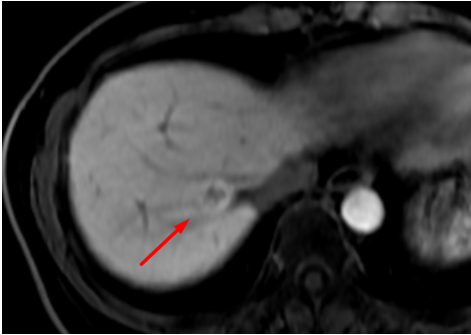

Hình ảnh bệnh nhân chụp MRI gan mật với thuốc đối quang từ đặc hiệu tế bào gan